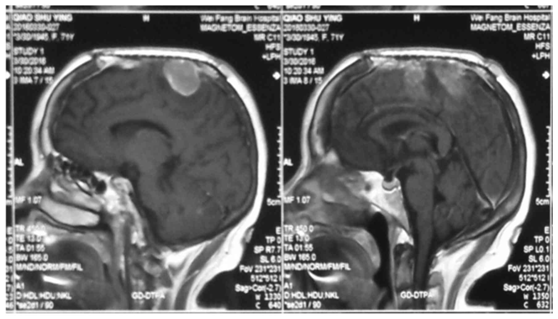

对此,INC国际神经外科医生集团旗下国际神经外科顾问团(WANG)成员、国际颅底肿瘤手术教授德国巴特朗菲教授指出,一般脑肿瘤都以手术切除为主,脑膜瘤也不例外,但其规模较大的难题仍是手术难以切除干净,较易复发,除了脑膜瘤本身的级别(WHO I级、II级、III级)以外,脑膜瘤切除的程度是影响脑膜瘤复发的一要素。特别是大脑镰和矢状窦的脑膜瘤,很多医生只切肿瘤,不切脑膜(因为肿瘤侵及矢状窦,这是静脉窦,容易出血,切除脑膜难度高),手术难度相对较大,完全切除干净的难度也大,特别是如果能将大脑镰、脑膜一并切除,复发的可能性较低。

巴特朗菲教授在脑膜瘤顺利及高切除率手术方面尤为擅长,他对于包括脑膜瘤在内的各种颅底脑内外病变手术切除都游刃有余。国际各地的想要追求较高手术质量的脑肿瘤患者慕名而来,想要巴特朗菲教授手术。

INC巴特朗菲教授手术全切脑膜瘤案例一则